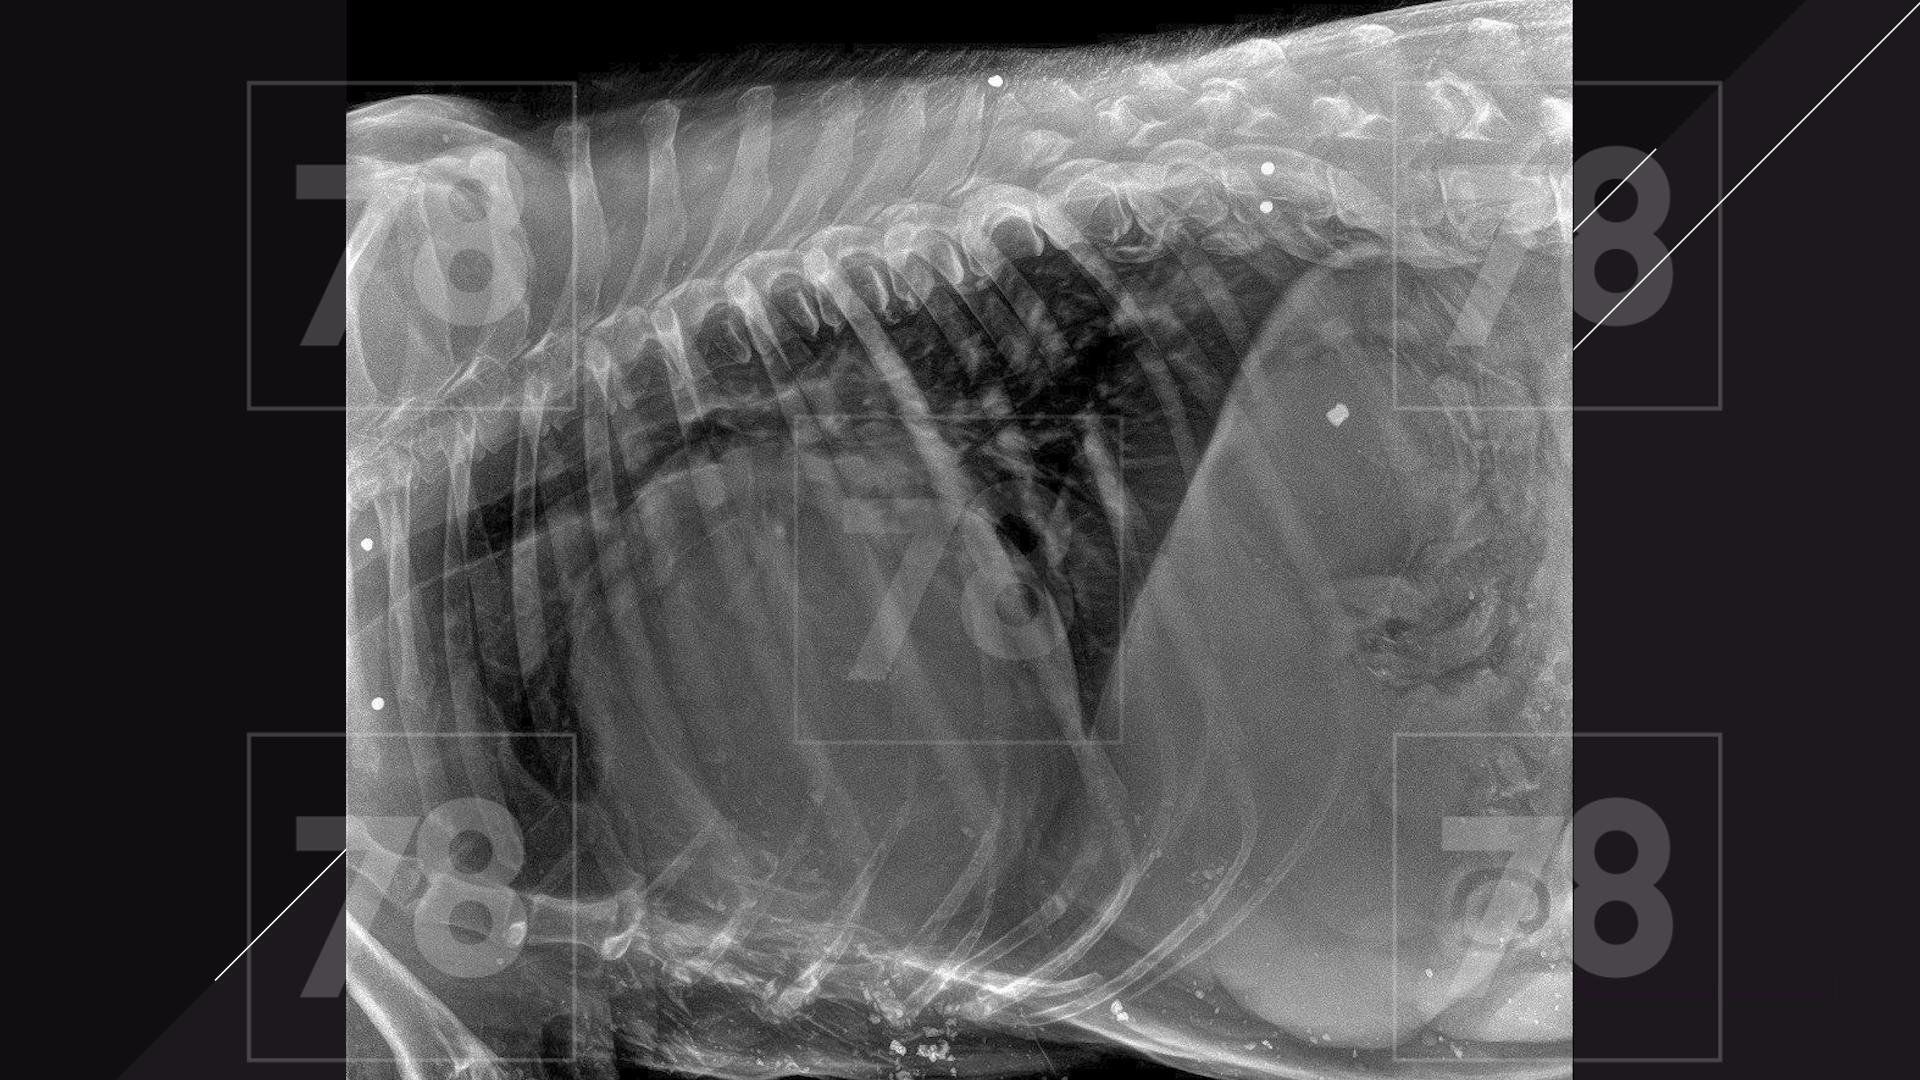

Врачи обнаружили у собаки множественные ранения пулями, как свежие, так и старые.